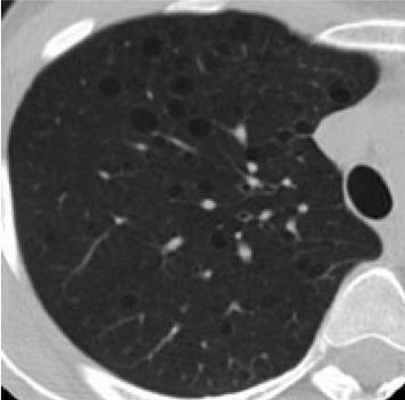

Фрагмент КТ: множественные кистозные изменения - лимфангиомиоматоз легких